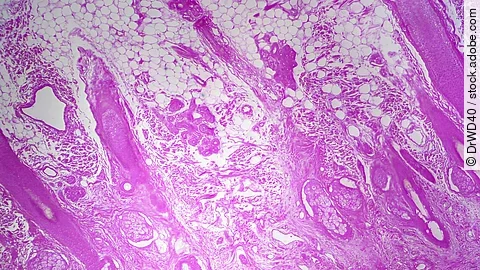

Die Jury des Händel-Tierschutzpreises würdigte bei ihrer Entscheidung, dass das Team um Peter Loskill und Silke Riegger bereits eine Vielzahl von Organ-on-Chip-Systemen als Ersatz- und Ergänzungsmethoden zu Tierversuchen für verschiedene Organsysteme entwickelt hat. Die Organ-on-Chip-Technologie basiert darauf, dass (Stamm-)Zellen bestimmter Gewebetypen in einem Zellkultursystem in einer mikrofluidischen Plattform angesiedelt werden. Aus den Zellen entwickeln sich verschiedene gewebespezifische Zellarten, wie etwa Herz, Netzhaut oder Niere. Ein differenziertes dreidimensionales Gewebe entsteht, das einem Organ in seiner Funktion und Architektur sehr viel näherkommt als eine einzelne Zellschicht. Über kleine Mikrokanäle, ähnlich zu Blutgefäßen, wird ein Blutersatz durchgespült. Integrierte Sensoren können dynamische Prozesse in den Mini-Organen auslesen und ermöglichen dadurch zum Beispiel Erkenntnisse über Wirkung und Verträglichkeit der getesteten Arzneimittel zu gewinnen. „Bereits jetzt gibt es einzelne Gewebe und Organe, die wir schon sehr gut im Labor nachbilden können, wie etwa die Netzhaut des Auges“, erläutert Loskill die Anwendung. „Damit untersuchen wir zum Beispiel Arzneimittelkandidaten zur Behandlung von Erkrankungen des Auges oder Ursachen von unerwünschten Nebenwirkungen, die zum Erblinden führen können“, führt er weiter aus.